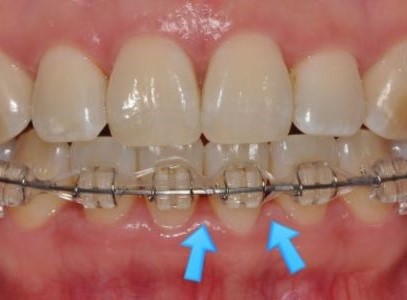

치간공극(블랙 트라이앵글)을 줄이기 위해

또 하나 중요한 이유는 바로 치간공극(Black Triangle, 블랙 트라이앵글) 문제입니다.

치간공극이란

치아와 치아 사이를 채워야 할 잇몸(유두)이 위로 올라가거나 줄어들면서

치아 사이가 검게 비어 보이는 삼각형 모양의 공간을 말합니다.

이때 치간삭제를 시행하고 공간을 다시 닫아 주면서

블랙 트라이앵글이 완전히 사라지지는 않더라도

눈에 띄게 크기가 줄고, 치아 사이가 더 긴밀하게 붙어 보이는 효과를 얻을 수 있습니다.